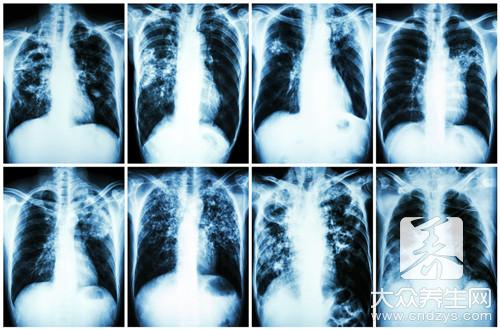

间质性肺纤维化是一种肺病,这种疾病可能和我们男性朋友经常抽烟有很大的关系,烟中富含了很多的尼古丁,尼古丁会对于我们自身的肺部产生很大的伤害,...